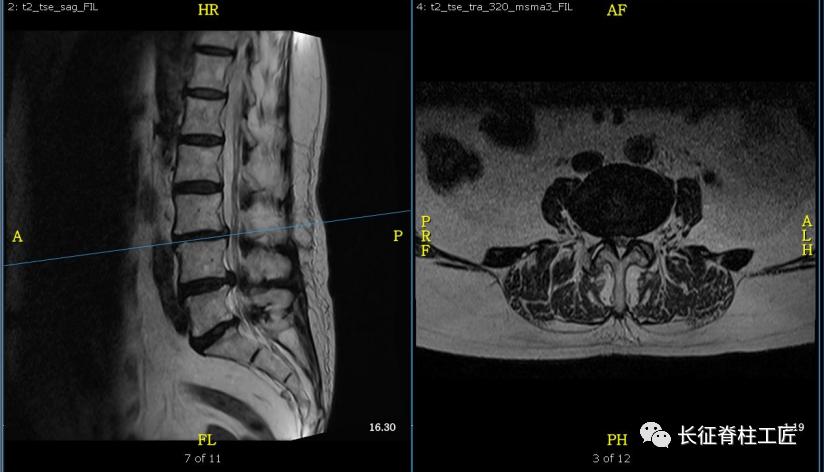

入院检查,腰部疼痛,后伸时加剧,局部压痛,双下肢肌力减退。X线检查,L4、L5骨质增生,MRI显示L4/L5、L5/S1椎间盘突出,马尾神经受压明显,被确诊为腰椎管狭窄症。

马尾神经是脊髓和周围神经的桥梁,脊髓的末端一般位于第2腰椎水平(腰椎共5节),脊髓末端就接着马尾神经,第2腰椎以下的腰椎管狭窄或腰椎间盘突出,压迫马尾神经,就会产生马尾神经综合征。

马尾神经综合征早期表现为会阴部麻木、感觉减退。当出现大小便功能障碍时,提示神经功能已经严重损害,应该立即采取急诊减压手术治疗,解除对马尾神经的压迫,尽可能挽救马尾神经功能。